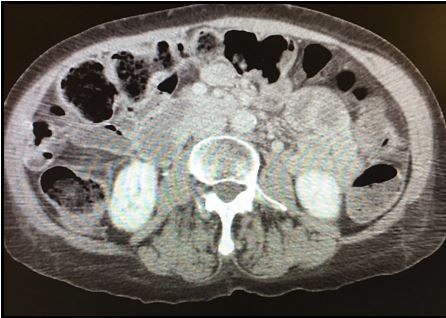

Figure 1. Abdominal CT scan

Results of a CBC, basic metabolic panel, serum lipase measure, and LFTs are all normal. Image of CT scan is shown in Figure 1 above (please click on image to enlarge).

Bowel wall thickening has a number of potential causes, some dangerous and others less so. The normal thickness of the bowel wall is <2mm; >3mm is considered abnormal; and 2-3mm is the equivocal range. Most causes of thickened bowel wall are infectious or inflammatory (predominantly Crohn disease and ulcerative colitis) and these both typically present with diarrhea. Small bowel obstructions can cause bowel thickening and this may be a sign of ischemia. Ascites and/or portal hypertension can cause chronic bowel wall thickening, which is usually benign and is likely the cause in this case. Refer to Figure 2 for other, less common causes.